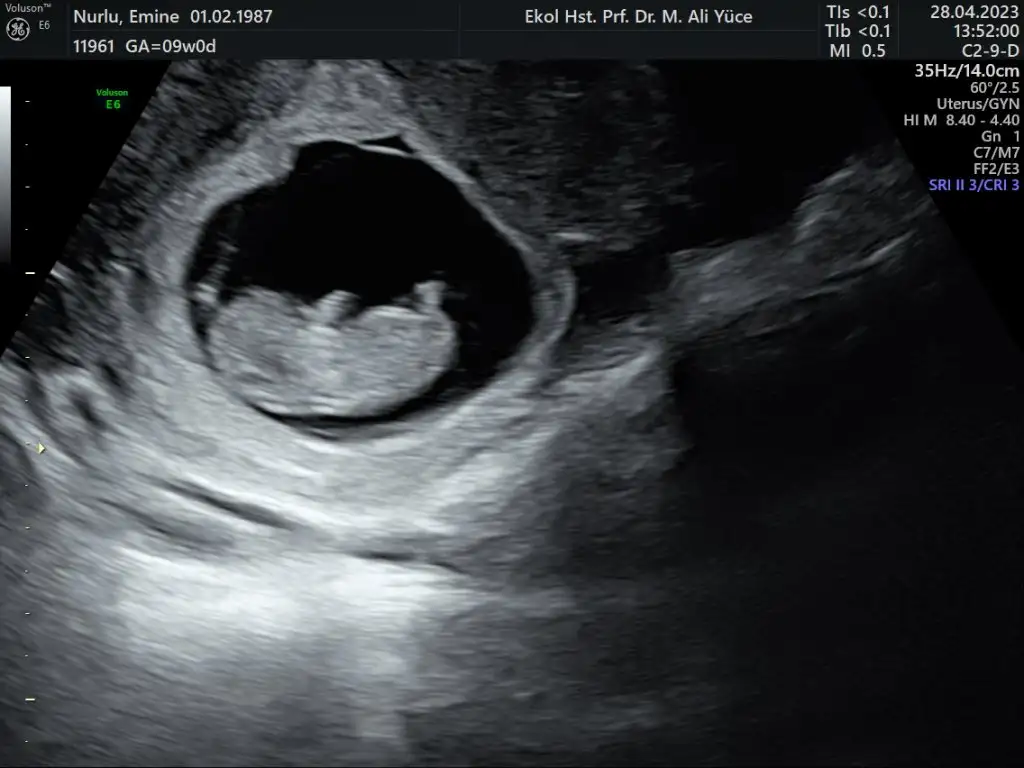

Ben de sürpriz 3.bebeğimle Kasım ayı anne adayıyım. muhtemel doğum tarihi 1 aralık ancak önceki doğumlarımın sezeryan olması nedeniyle Kasım ayında doğum olacağını söyledi doktorum. Umarım hepimiz sağlıkla kucağımıza alırız. Endişelerimden yeni yeni kurtulup aranıza katılabiliyorum. Bugün 11+6 yım. bir sonraki kontrolüm haftaya salı günü. en son 9 haftalıkken gitmiştim. diğer gebeliklerimle belirtiler konusunda hiçbir farklılık yaşamıyorum. (iki oğlum var) fotoğraf eklesem ben de cinsiyet tahmini alabilir miyim